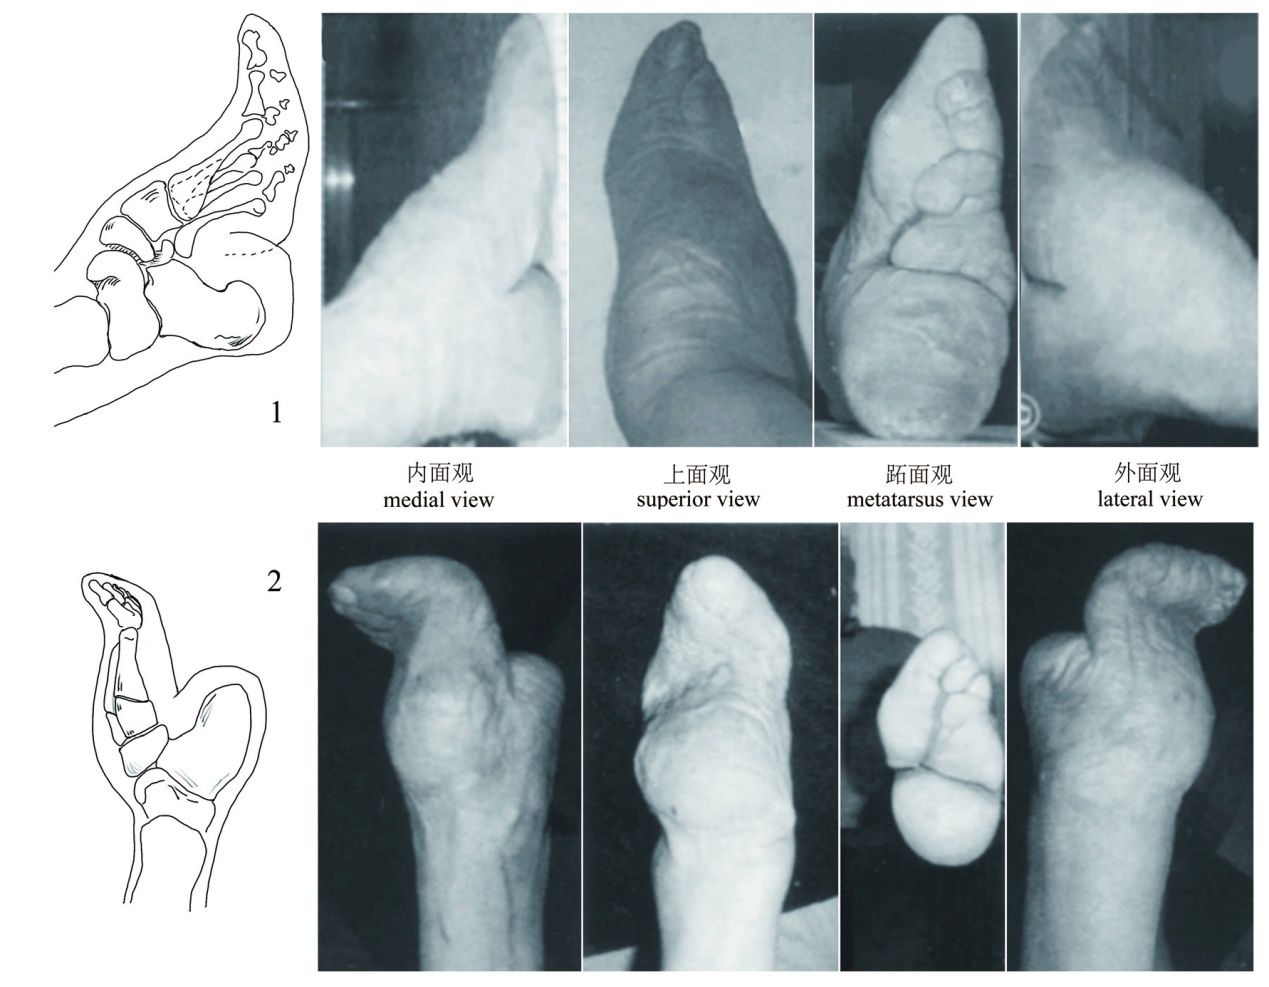

图2 缠足女性足骨形变示意图[10] 1. 趾骨骨体缩窄 narrowing of the proximal phalangeal bone; 2. 第5跖骨头形态多变 diverse fifth metatarsal head; 3. 楔骨整体尺寸缩小 cuniform with reduced overall size; 4. 足舟骨呈倒勾状 hook-shaped pontine tuberosity; 5. 跟骨最小宽明显缩小 significant reducing of the minimum width of calcaneus; 6. 距骨后跟关节面边缘缩小 the facet at the edge of the articular surface of talus heel; 7. 跟骨结节上缘关节面呈斜坡状 clivus articular surface of the superior edge of calcaneal tubercle

Fig.2 Schematic diagram of foot bone deformation of women with foot binding